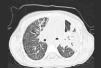

O estudo laboratorial revelou aumento da contagem leucocitária 19.7×109/L; 73% de polimorfonucleares e 19.4% de linfócitos e Proteína C-reativa: 284.4mg/L; radiografia torácica revelou consolidação à esquerda ocupando o seio costofrénico e a ecografia torácica mostrou um pequeno derrame pleural. A Tomografia axial computorizada (ver fig. 1) revelou derrame pleural esquerdo, infiltração alveolar do lobo superior esquerdo com áreas de cavitação do segmento póstero-superior associado ao processo necrótico.